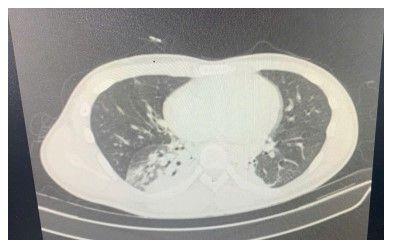

Hình ảnh chụp CT-Scan viêm đông đặc thuỳ phổi